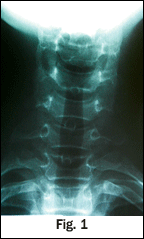

On the first spinal manipulation, he experienced a sudden increase in cervical tone of the left SCM, and reported a sudden decrease in pain with motion. No new pain with radiation into or down his left arm or with numbness in his fingers developed, nor did he develop any weakness in his left hand. He was seen subsequently for 12 conservative measures; 50 percent of the time he received spinal adjustments and he did improve. There was an indication of a relative contraindication to CSMT based upon the disease process. He previously had undergone radiological imaging, which revealed an antalgic list (Fig. 1), sigmoid-type curve and loss in cervical lordosis and a slight segmental flexion and anteriolisthesis (Fig. 2), consistent to a whiplash or CAD injury presentation. Cervical oblique (Fig. 3-4) failed to demonstrate any cervical stenosis. Open-mouth odontoid or dens (Fig. 5) failed to demonstrate any developmental deficiencies of the cervical spine, i.e., agenesis or odontoid hypoplasia. A low-force technique mode was chosen and discussed with the family. At the conclusion of care, the patient had experienced a complete recovery of his acute pain state.